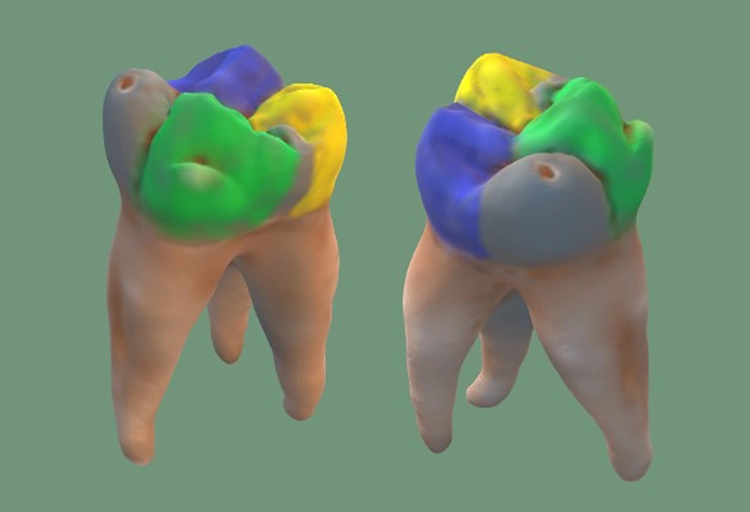

Auf kreative Weise die Zahnmorphologie besser erfassen

In der Ausbildung oder bei internen Workshops auf spielerische Weise durch kreatives Schaffen in die Eigenverantwortung zu kommen, macht nicht nur Spaß, sondern bietet zudem großes Lernpotenzial. ZT Michaela von Keutz zeigt 3 Varianten auf, die sie in ihren zahntechnischen Fortbildungskursen nutzt, um das handwerkliche Können rund um die Morphologie des Zahnes bei den Teilnehmern in den Fokus zu rücken.